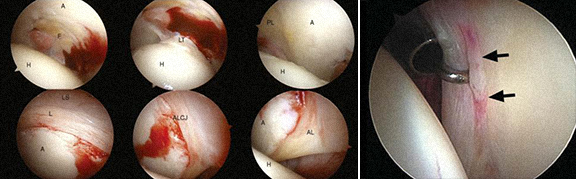

· As lesões intra-articulares são geralmente tratadas por artroscopia (rotura do labrum, lesão da cartilagem, rotura do ligamento redondo, corpo livre, sinovite, condromatose, quisto intraarticular, artrite séptica, alguns casos de prótese da anca dolorosa).

1 - Rotura do labrum 2 – Delaminação da cartilagem

3 - Corpos livres visíveis nas imagens de Rx e TAC, e extração por artroscopia

4 - Quisto intra-articular - exérese

5 - Prótese da anca dolorosa – exérese de tecido fibroso, causa de dor e de mau funcionamento da prótese.

6 – Sinovite vilonodular – exérese de vilosidades.